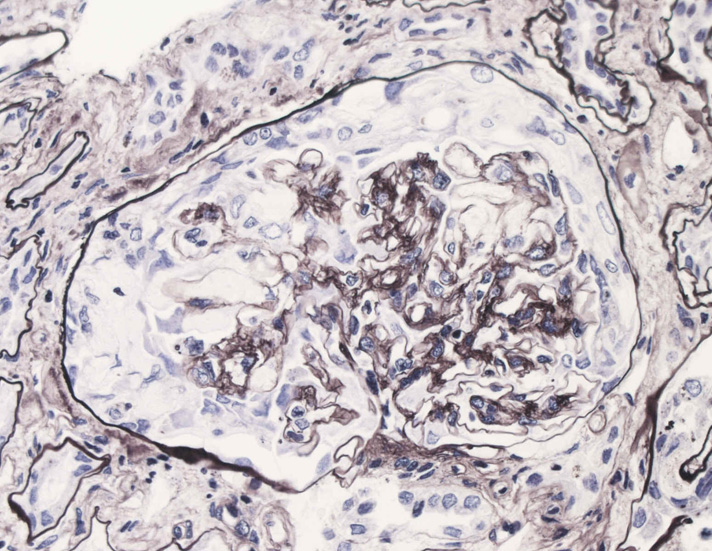

腎臓の病理組織所見-->壊死性糸球体腎炎

kidney04pas.jpg

kidney05.jpg

kidney06.jpg

Fig.03(PAS)Fig.04(PAM染色)Fig.05(PAM染色)